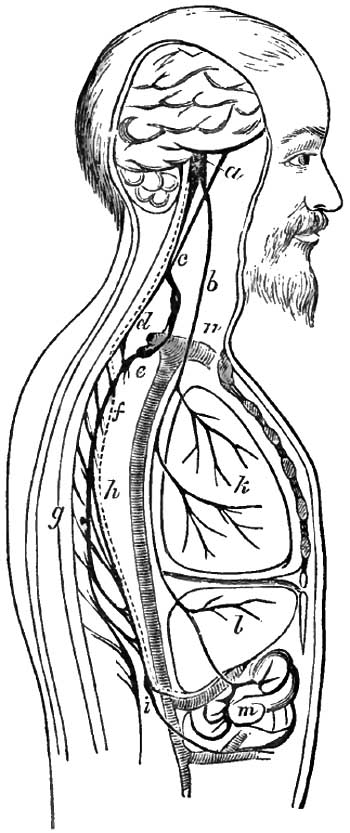

| 4. | DIAGRAM SHOWING ANOTHER COURSE WHICH THE VASO-MOTOR NERVES OF THE LIVER MAY TAKE |